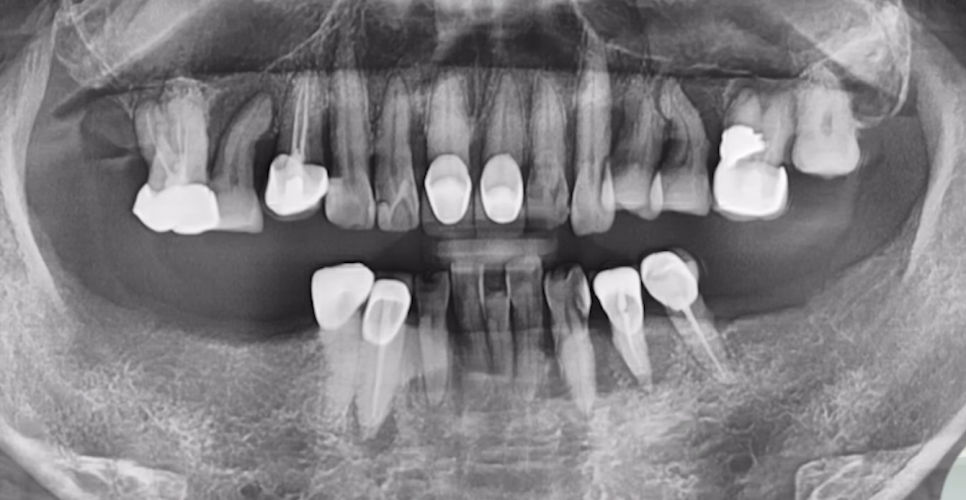

61세 남성 환자분이셨고

임플란트를 심기에는 전체적으로 염증이 많이 퍼져 있는 상태였습니다.

하여 발치를 결정한 치아들은 순차적으로 발치를 다 해드렸고,

염증 제거와 잇몸뼈 회복이 우선이었기에

뼈가 어느 정도 아물 때까지 3개월 정도 기다렸습니다.

그런데 사실상 남아 있는 뼈들도 부족한 상태고,

임플란트 심기에는 상악동 뼈도 굉장히 얇은 상태입니다.

이런 상태에서는 무리하게 식립하다가

임플란트가 상악동에 빠지는 사고가 발생할 수도 있습니다.

당일에 뼈이식과 상악동 뼈 이식을 해드려 뼈를 충분히 보강한 후, 동시 식립까지 진행했습니다.

상악동에 뼈 잘 이식된 것 보시이죠?

CT 사진으로 잘 식립된 것까지 체크해 드린 후 다음 날 반대편까지 안전하게 심어드렸습니다.

물론 시간은 조금 더 걸렸지만,

잇몸선도 안정적이고 보철물 심미성도 좋게 나왔는데요.